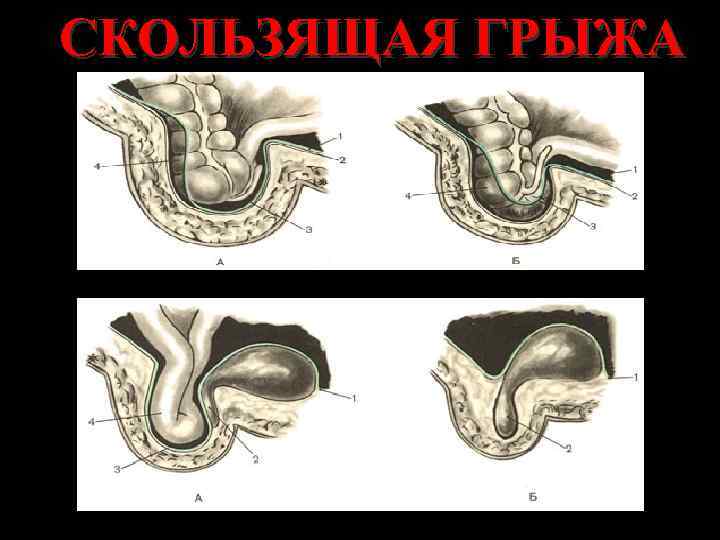

СКОЛЬЗЯЩАЯ ГРЫЖА